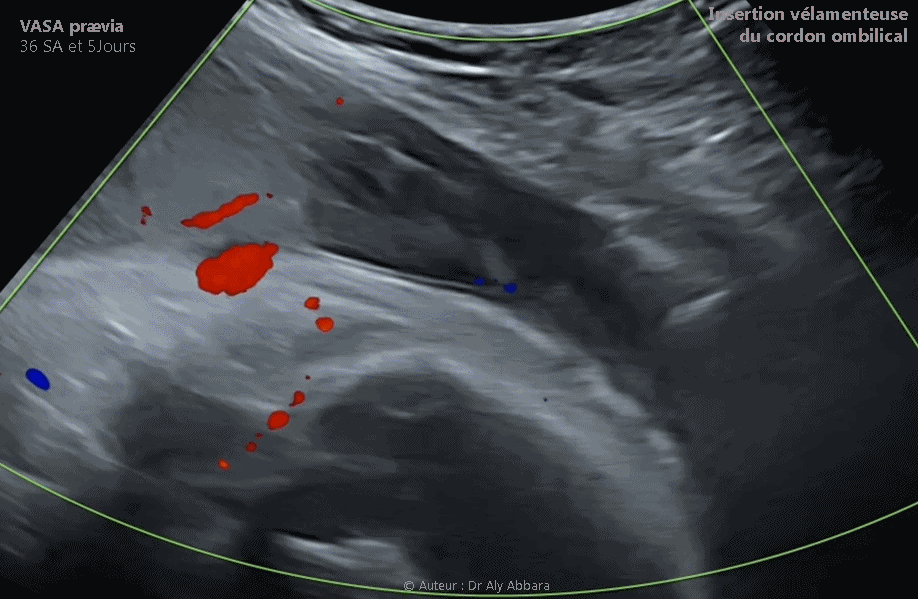

Vaisseaux praevia associés à une insertion vélamenteuse du cordon - grossesse de 36 SA

Placenta d'une grossesse de 36 SA et 3 jours caractérisé par l'insertion vélamenteuse du cordons ombilical ; les vaisseaux sanguins reliant le cordon au placenta sont praevia et traversant l'orifice interne du col utérin

• Images échographiques et cliniques animées montrant la présence de vaisseaux prævias (vasa prævias) reliés au bord inféro-antérieur du placenta et traversant le segment inférieur de haut vers le bas, et de la gauche vers la droite ; dans ce trajet diagonal, une artère et une veine passent exactement devant l'orifice interne du col utérin.

• Ce diagnostic échographique de vasas prævias a été fait au terme de 33 SA, lors de l'échographie habituelle du 3° trimestre.

• La césarienne programmée a été réalisée à 38 SA a confirmé le diagnostic de vasas prævias et a montré que cette pathologie est due à une insertion vélamenteuse du cordon ombilical sur les membranes amniotiques recouvrant le pôle inféro-postéro-latéral droit de la cavité utérine, et comme l'a montré l'échographe anténatale, les vaisseaux sanguins reliant le cordon ombilical au pôle antéro-inférieur du placenta prenaient une position prævia sur le segment inférieur de l'utérus dont une veine et une artère passant devant l'orifice interne du col utérin, avec un risque majeur de rupture vasculaire au cours du travail et d'hémorragie de Benckiser.